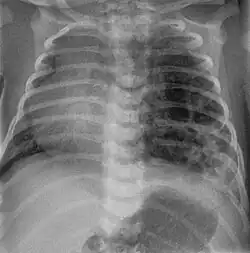

Pulmonary hypoplasia

Fetal conditions can also cause a mediastinal shift during development. For example, pulmonary hypoplasia is the underdevelopment of a lung due to various etiologies. These include agenesis due to gene mutation, fetal hydrothorax, and congenital diaphragmatic hernia. These conditions lead to incomplete development of lung tissue or hypoplasia. This can be unilateral or bilateral and is seen on x-ray as a mediastinal shift towards the side of the underdeveloped lung.[15][16] Additionally, mediastinal shifts can also be detected using antenatal ultrasonography.[17]